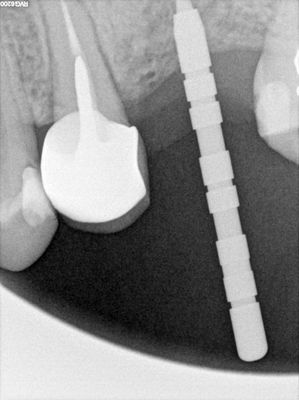

small sinus lift with densah drills, no membrane perforation.